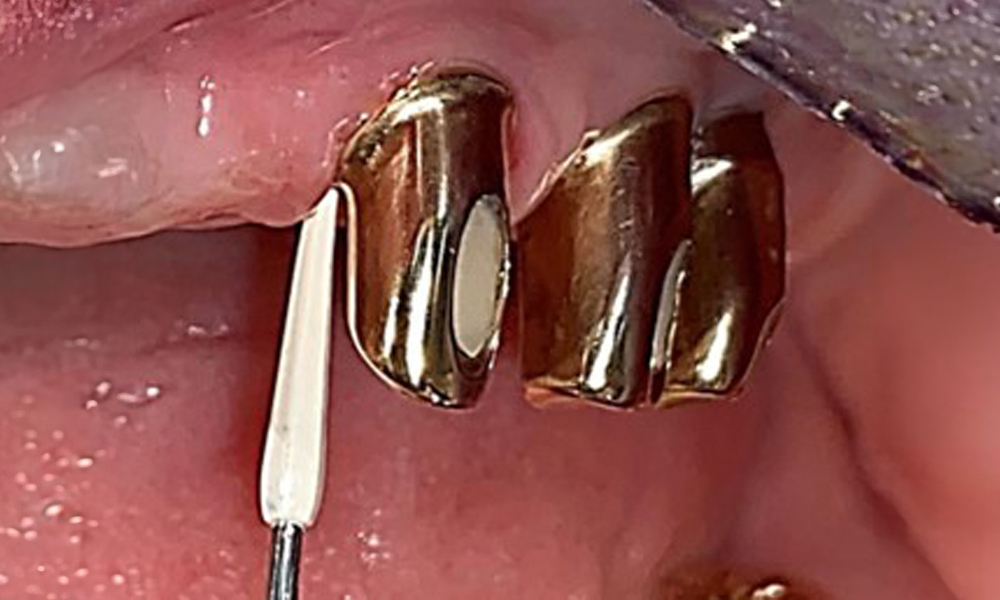

Frontal view with the maxillary denture in situ.

Fig. 1: Frontal view with the maxillary denture in situ.

The patient was fitted with a combined removable maxillary telescopic prosthesis more than 25 years ago (Fig. 1, Fig. 2, Fig. 3) and is very happy with her dentures. The patient has an adequate fixed denture for the mandible (Fig. 4).

The dental findings are as follows: Combined removable implant and tooth-supported telescopic prostheses on implants 15, 13, 21, 23, 24, 25 and tooth 11 (Fig. 1, Fig. 2, Fig. 3). The patient was fitted with a fixed mandibular denture. Adequate bridges were present over 37 to 34 and 45 to 47 (Fig. 4), the crown margins were intact and there were no active caries. A composite filling with a marginal gap was present on tooth 43. There was mandibular gingival recession, exposing 1 to 3 mm of root surface. This also applies to 11.